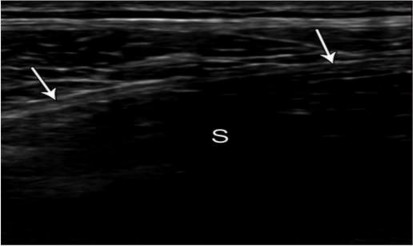

Tiến hành siêu âm sau 1 năm nhằm: khảo sát, đánh giá mô xơ tạo thành sau đặt tấm lưới nhân tạo polypropylene ở vùng bẹn, dựa vào nguyên lý: vùng phía trước tấm lưới xuất hiện đường tăng âm, phía sau tấm lưới là dải bóng đen.

Hình 2.10. Tấm lưới ở vùng bẹn phải. Siêu âm khó nhìn thấy và xuất hiện với đường tăng âm nhỏ (mũi tên) với dải bóng đen ở phía sau (S). Nguồn: Jamadar D. A., Jacobson J. A., (2008) [74].